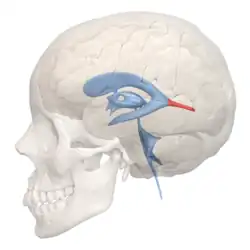

Drawing of a cast of the ventricular cavities, viewed from the side; oriented facing right. | |

Drawing of a cast of the ventricular cavities, viewed from above

Drawing of a cast of the ventricular cavities, viewed from above